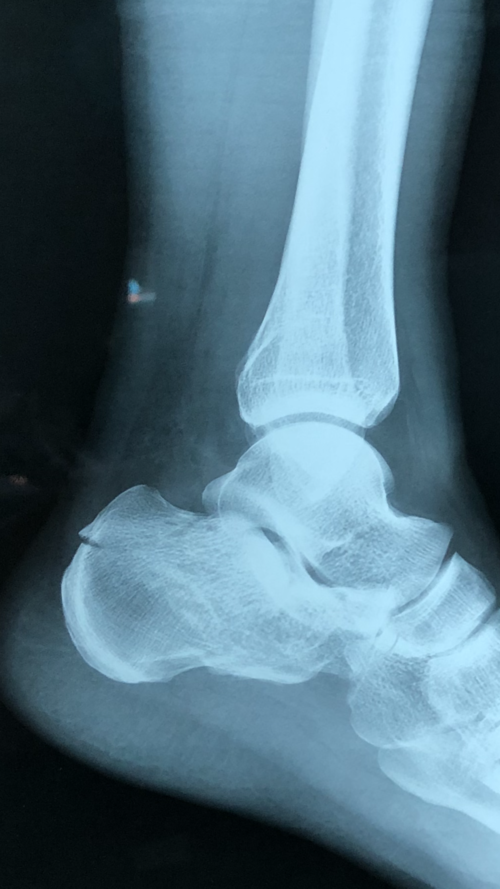

男42岁,跟骨骨折

请问我的这种跟骨粉碎性骨折如何康复才能最大的降低创伤性关节炎的

跟骨骨折病例分享

跟骨骨折87天了专家们给看看!